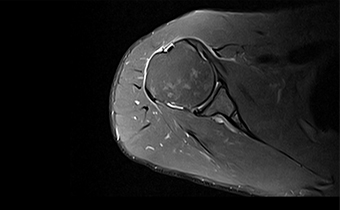

高均匀度磁体

呈现大FOV、偏中心优质图像;实现大范围压脂成像,缩短压脂序列时间

一体化线圈

无需更换线圈,即可进行多部位联合成像,缩短检查时间。

真32通道系统

多通道线圈与多通道谱仪一一独立对应,配合快速并行采集技术改善成像速度。

智能全数字化

光纤传输

采集系统,梯度系统,射频系统全部数字化,光纤传输,有效减少信号衰减,避免干扰,改善信噪比。